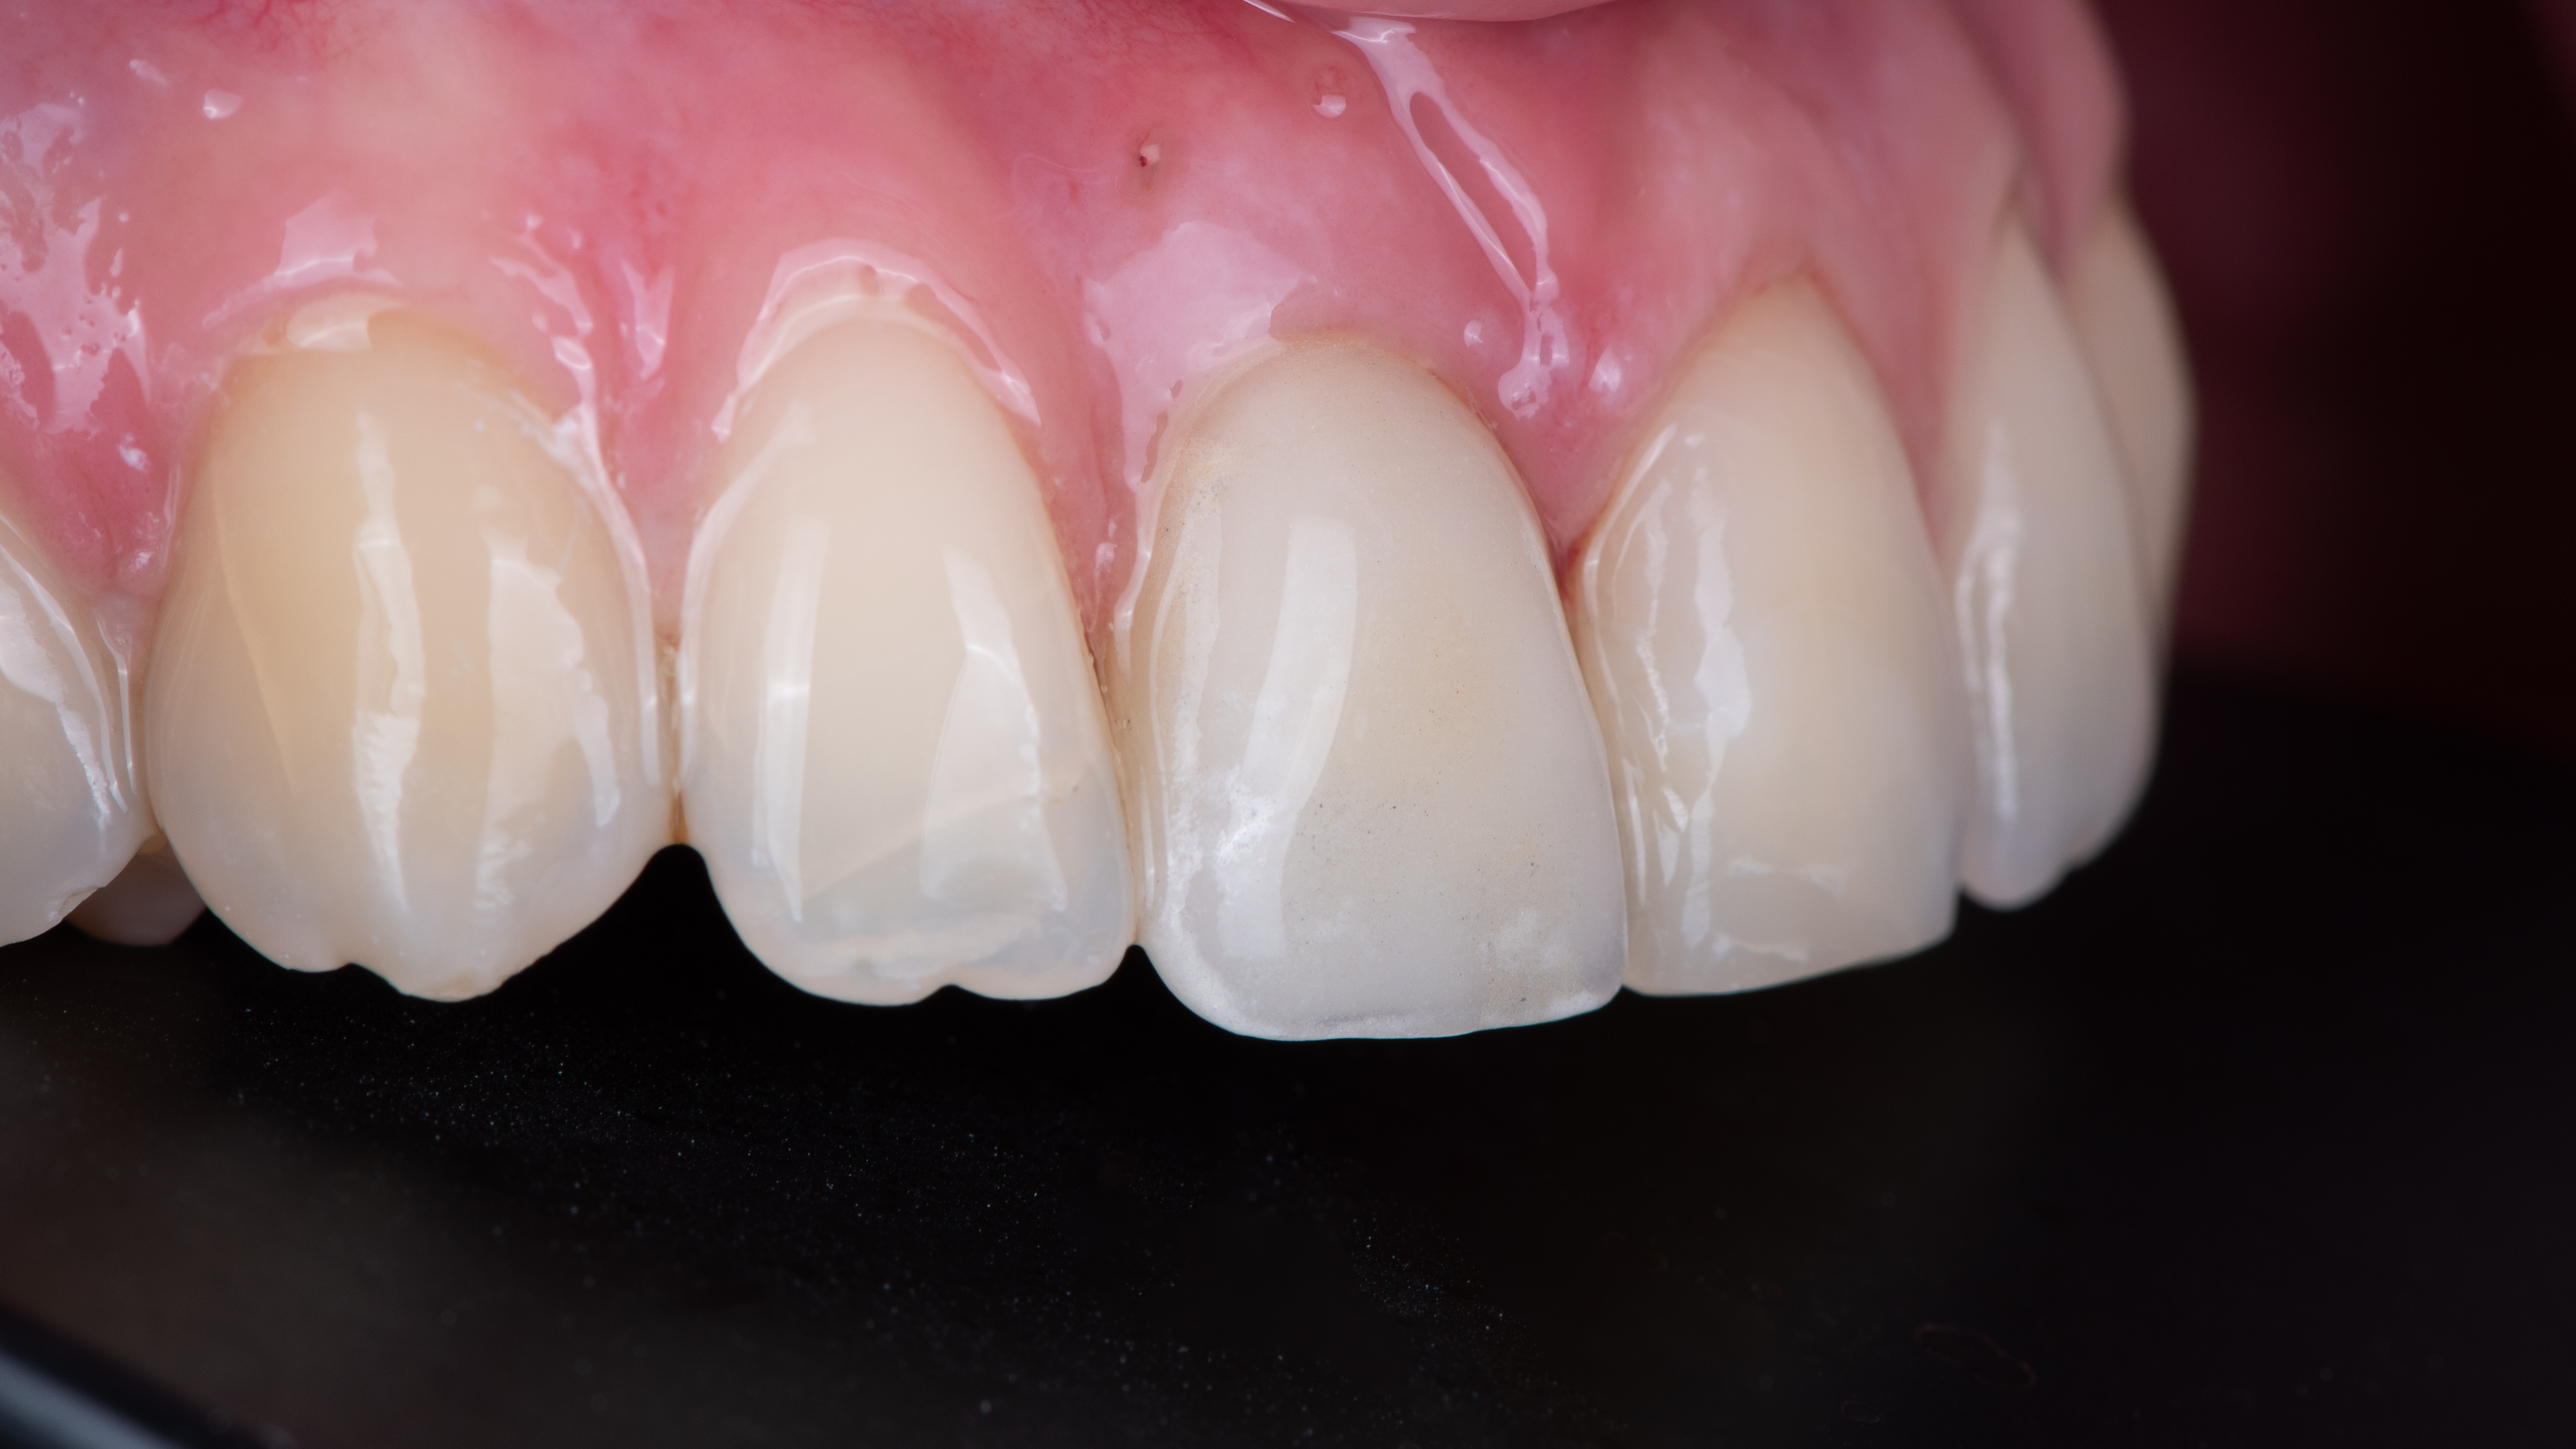

Nous constatons que la cicatrisation est alors optimale et que la prothèse d’usage s’intègre parfaitement à son environnement (Photo 20).

Intégration des réhabilitations au niveau du sourire de la patiente (Photo 26).